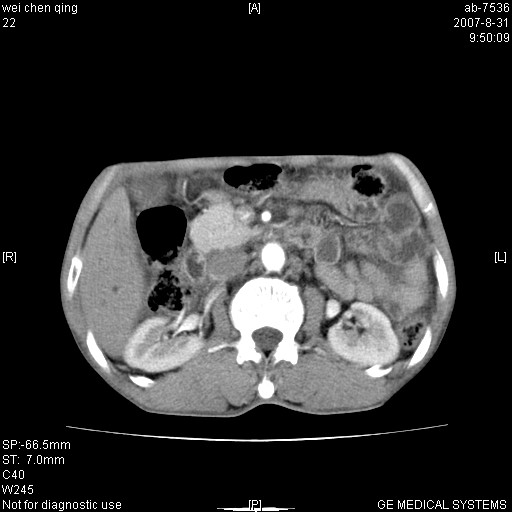

以下是引用zyyzzy在2007-8-31 14:34:00的发言:[br]该病人肝内胆管扩张,胆囊及胆总管未见明显扩张。在倒数第9层图像上可看到左右肝管结合部(肝总管)有软组织影,此处应薄层扫描。考虑肝总管占位(ca)、腹水。[br]